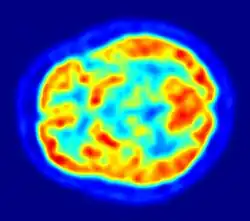

Im Gegensatz zu den auf Transmission basierenden Tomografieverfahren beruht die Bildentstehung bei PET und SPECT auf Emission und bildet somit die Verteilung des zuvor injizierten Radiopharmakons im Körper ab. Daraus ergibt sich eine primär funktionelle Abbildung und erst in zweiter Linie, in Abhängigkeit von der dargestellten Funktion, eine morphologische Abbildung. Deshalb liegt die Bedeutung der Anwendung von PET u. a. in der Beantwortung von Fragestellungen nach Stoffwechselvorgängen (z. B. Glukosestoffwechsel), Rezeptorstatus (z. B. Dopamin-Rezeptoren), oder Oberflächen-Antigen-Eigenschaften (z. B. PSMA-Status). Wichtige, klinische Anwendungen liegen in der Onkologie, Neurologie sowie Kardiologie.

Der Nobelpreisträger für Physiologie oder Medizin Otto Warburg erkannte schon im Jahre 1930, dass Tumorzellen aufgrund eines erhöhten Stoffwechsels meist mehr Glucose verbrauchen als normale Körperzellen (Warburg-Effekt). 18F-Fluordesoxyglucose (FDG) wird über den Glucosetransporter von Zellen genauso aufgenommen wie Glucose, obwohl an einer Stelle des Moleküls eine Hydroxygruppe durch das Radionuklid 18F ersetzt ist. Da das im nächsten Stoffwechselschritt intrazellulär aus der Phosphorylierung von FDG entstehende FDG-6-Phosphat nicht weiter verstoffwechselt wird, findet eine Anreicherung statt („metabolic trapping“), die proportional zum aktuellen Stoffwechselzustand der Zellen ist. Dies ist besonders für die frühe Diagnose von Krebserkrankungen von Vorteil, wenn noch keine tumorbedingte Größenzunahme erfolgt ist, die für die Erkennung in anderen Schnittbildverfahren notwendig ist. Die Verteilung von FDG im Körper erlaubt neben dem Auffinden von Tumoren und Metastasen aber auch generell Rückschlüsse auf den Glucosestoffwechsel von Geweben. Das Anreicherungsprinzip anderer Radiopharmaka gehorcht ähnlichen Mechanismen: Wo immer das Radiopharmakon angereichert wird, wird dies durch einen erhöhten radioaktiven Zerfall an dieser Stelle im PET-Bild sichtbar. Cholin wird für die Biosynthese von Zellmembranen benötigt. In den Zellen wird Cholin phosphoryliert und als Phosphorylcholin in Phospholipide eingebaut. Tumorzellen haben durch ihre schnellere Vermehrung einen erhöhten Bedarf an Cholin. Als Cholin-Tracer werden [18F]Cholin und [11C]Cholin benutzt. Thymidin-Tracer eignen sich zur Markierung von DNA, die von Tumorzellen verstärkt verdoppelt wird. Man benutzt hierfür 14C-, 3H-, 11C- und 18F-markiertes Thymidin, die wie natürliches Thymidin in die DNA eingebaut werden.